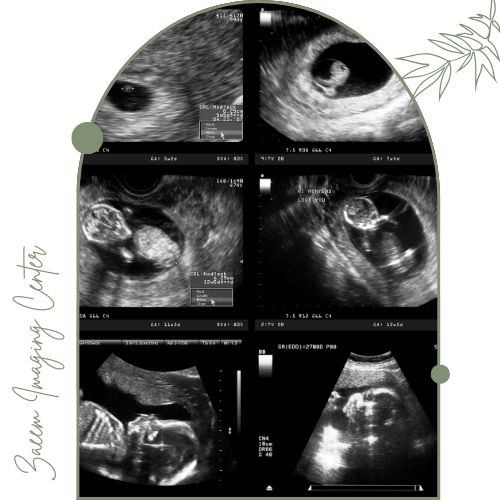

در این مرکز دستگاههای نسل جدید سونوگرافی مطابق استانداردهای جهانی برای بررسی ساختار اندامهای جنین مورد استفاده قرار میگیرند. این تجهیزات توانایی ارائه تصاویر با وضوح بسیار بالا را دارند و امکان تشخیص دقیق ناهنجاریهای استخوانی، قلبی، مغزی و دیگر اندامهای جنین را فراهم میسازند.اطلاعات جمعآوری شده توسط تیم پزشکی مرکز به صورت تخصصی بررسی و گزارش میشوند تا روند تصمیمگیری و اقدامات پزشکی با اطمینان کامل انجام گیرد.